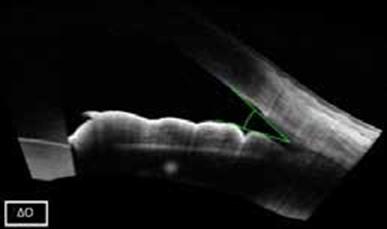

- Ωστόσο, κατά τον επανέλεγχο έξι μήνες αργότερα, ο κλινικοεργαστηριακός έλεγχος κατέδειξε σημαντική επιδείνωση του γλαυκώματος, με εμφανή επιδείνωση των παραμέτρων του οπτικού πεδίου και αξιοσημείωτη αύξηση της ημερήσιας διακύμανσης της ενδοφθάλμιας πίεσης (ΕΟΠ): ΔΟ:15 έως 21mmHg, AO:16 έως 28mmHg (Εικόνα 3)

- Η οπτική τομογραφία συνοχής πρόσθιου ημιμορίου (AS-OCT) έδειξε αύξηση του εύρους της γωνίας (Εικόνα 4)